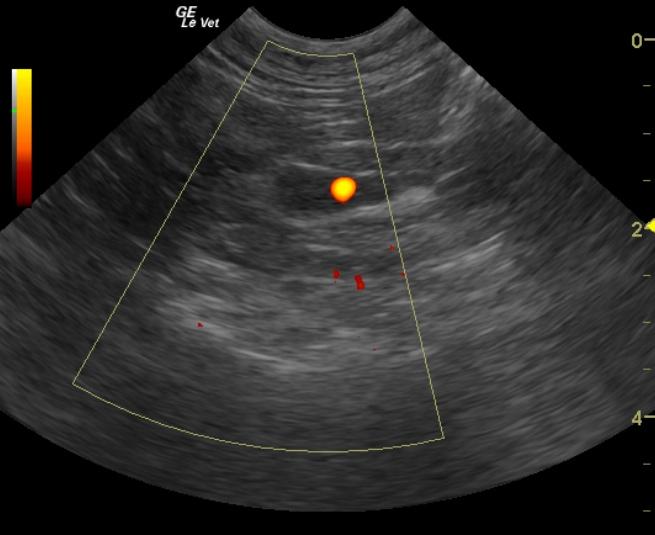

A 13-year-old FS DLH cat was presented to the clinic for the evaluation of a swollen abdomen, alopecia, and anorexia. The cat had a prior history of surgical correction of a corneal ulcer. The blood chemistry performed at the time of the corneal ulcer had shown a mild azotemia and hyperamylasemia. The CBC showed a low HCT, neutrophilia, and lymphopenia. The T4 was within normal limits. The urinalysis showed a pH within normal limits and a low specific gravity (1.013.) The urine had a clear, yellow appearance, but there was proteinuria (1+) and hematuria (3+) on the dipstick.

A 13-year-old FS DLH cat was presented to the clinic for the evaluation of a swollen abdomen, alopecia, and anorexia. The cat had a prior history of surgical correction of a corneal ulcer. The blood chemistry performed at the time of the corneal ulcer had shown a mild azotemia and hyperamylasemia. The CBC showed a low HCT, neutrophilia, and lymphopenia. The T4 was within normal limits. The urinalysis showed a pH within normal limits and a low specific gravity (1.013.) The urine had a clear, yellow appearance, but there was proteinuria (1+) and hematuria (3+) on the dipstick. The sediment confirmed hematuria with a RBC count of 4-10/HPF. Microalbuminuria was present. Repeat bloodwork revealed a marked azotemia, severely elevated creatinine, as well as hyperkalemia, hypermagnesemia, hyperamylasemia, and an elevated CPK. The CBC showed a thrombocytopenia and lymphopenia.